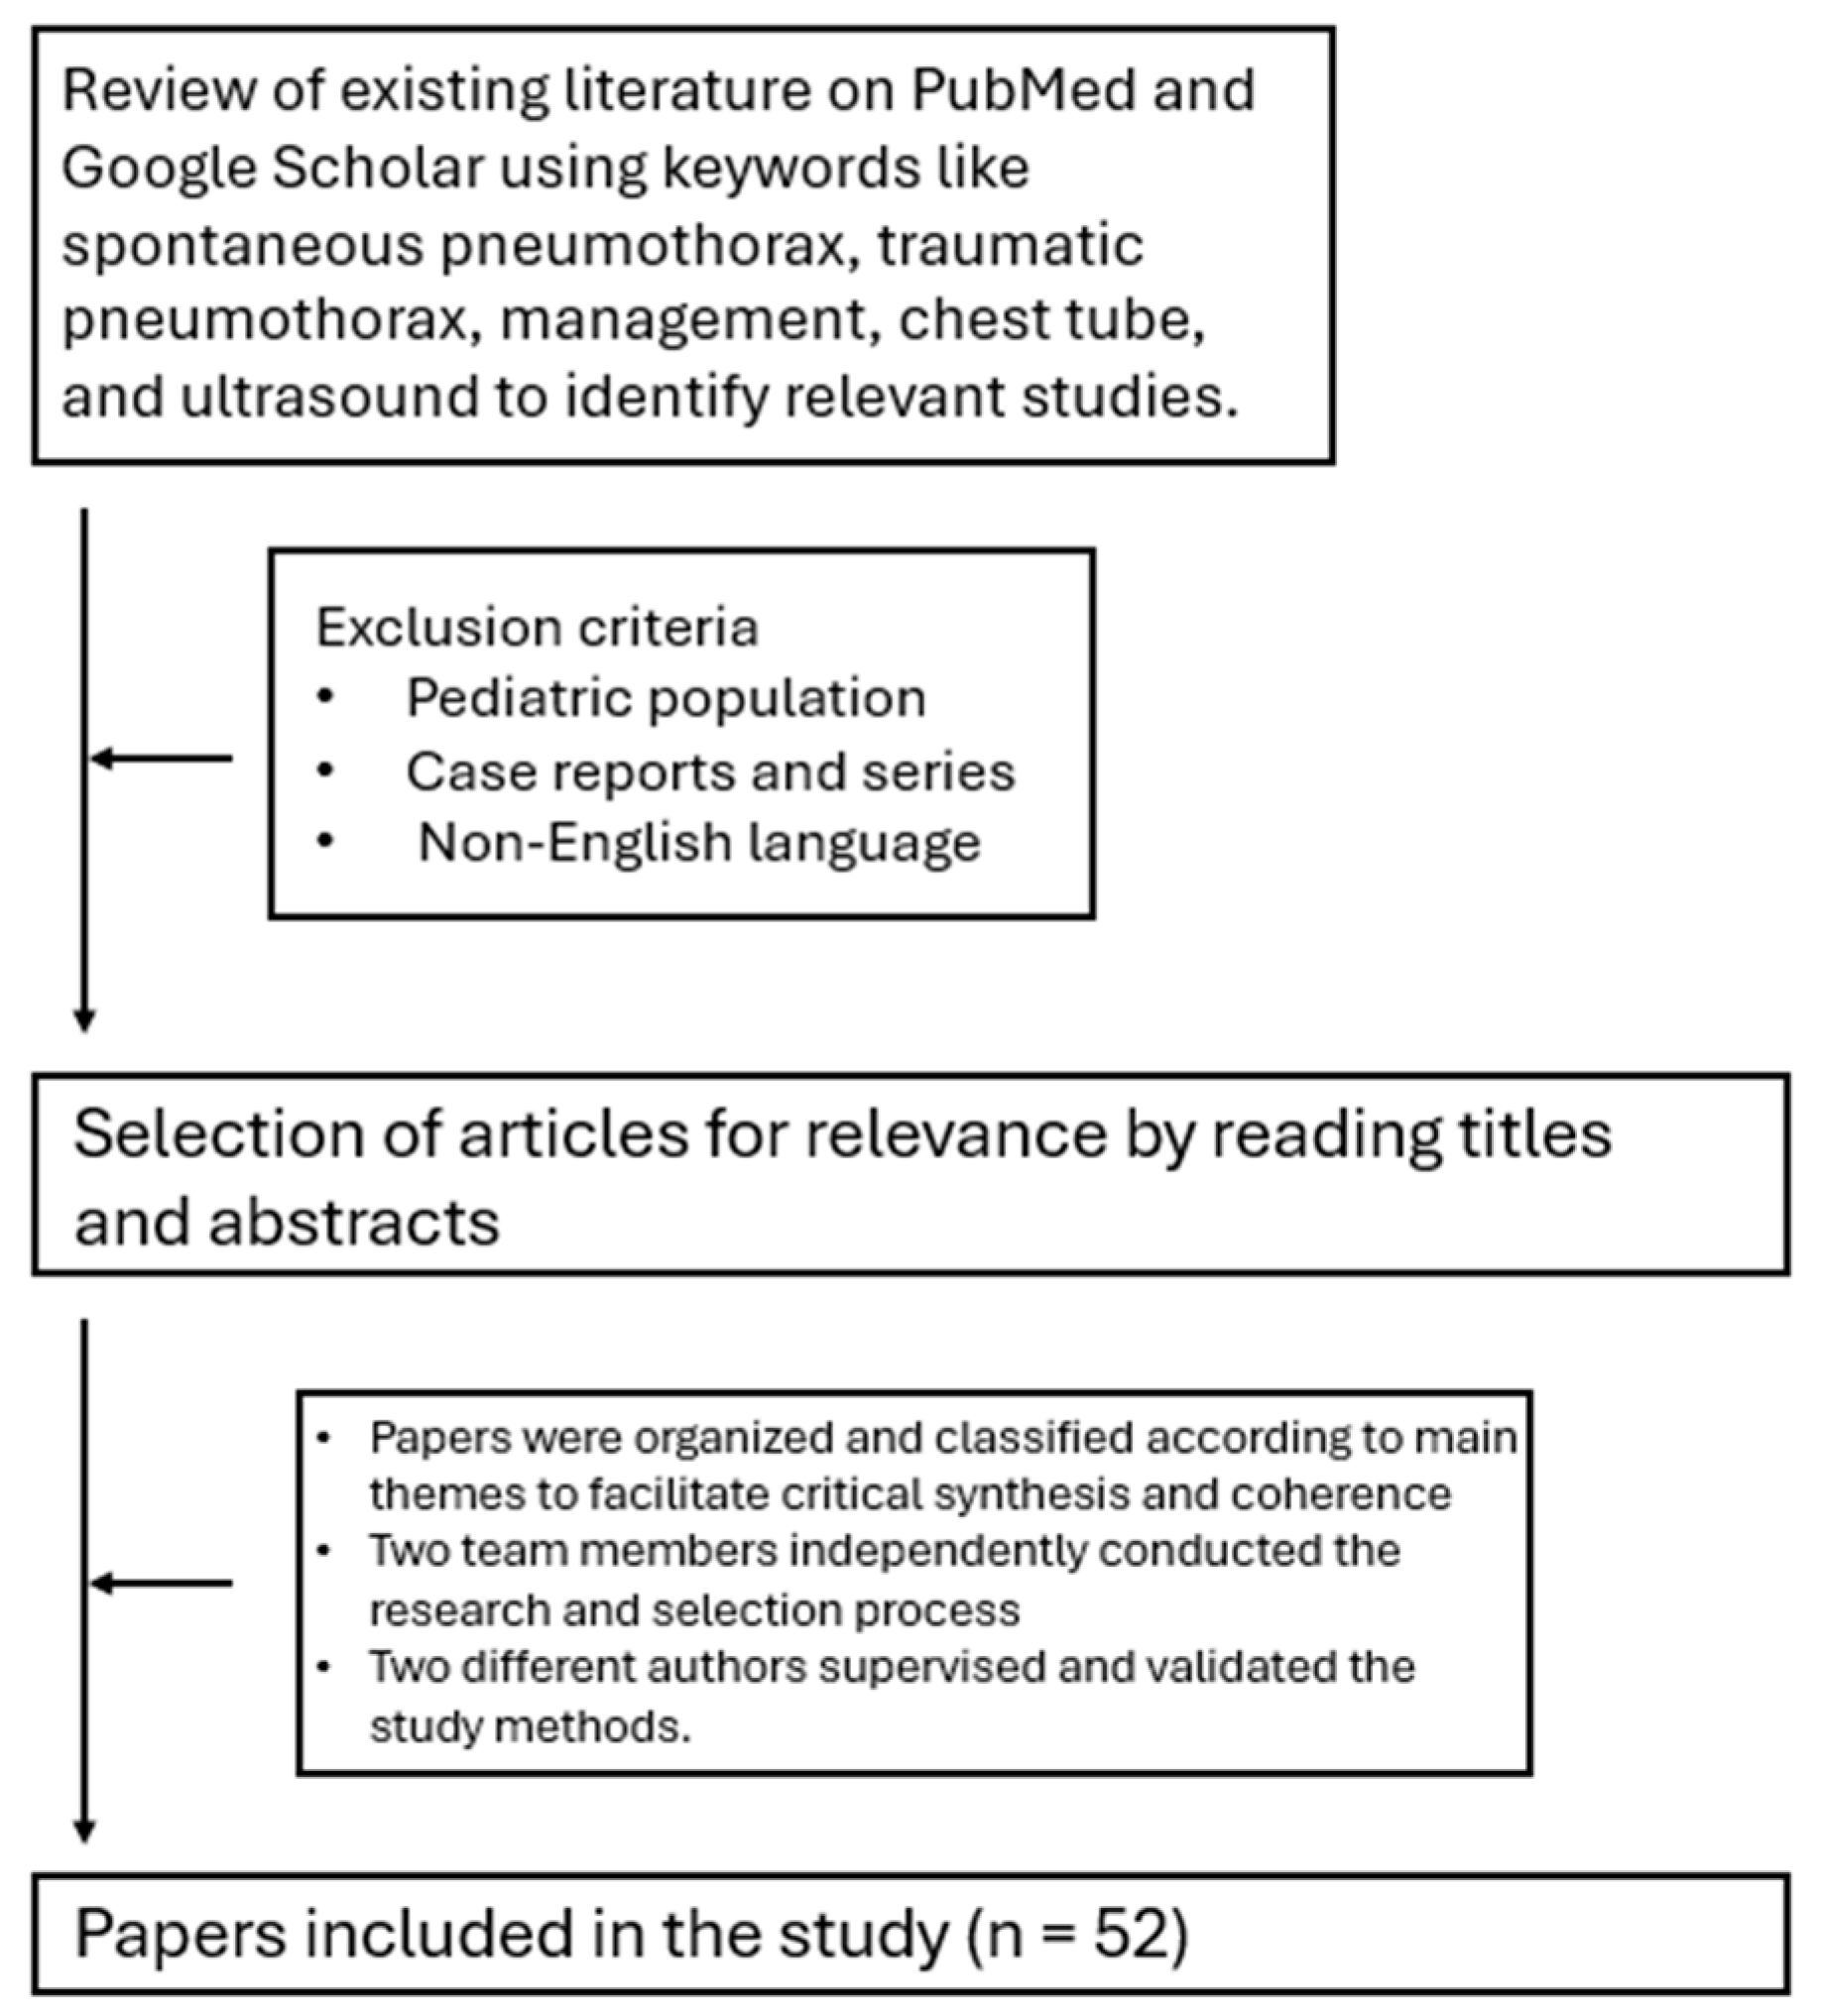

The Invisible Threat That Leaves You Breathless—A Literature Review on Pneumothorax in the Emergency Department

Abstract

:1. Introduction

3. Diagnosis

3.2. Ultrasound

- Absence of pleural sliding: Normally, the visceral pleura glides against the parietal pleura with respiration. In pneumothorax, this movement is absent;

- Absence of B-lines: Comet-tail artifacts (B-lines) are reverberation anomalies that disappear with the presence of air in the pleural space;

- Lung point sign: The point where normal lung sliding meets the absent sliding of the pneumothorax; this is highly specific for pneumothoraces;

- Barcode or stratosphere sign: A static, uniform appearance on M-mode ultrasound indicating loss of lung movement (Figure 3).